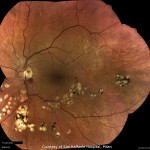

さまざまな

イメージングモダリティ

DRSplusは、TrueColor、レッドフリー、青色と赤色波長の画像、外眼部画像、ONHとステレオビュー、そしてモザイク画像といったさまざまなイメージングモダリティを提供します。